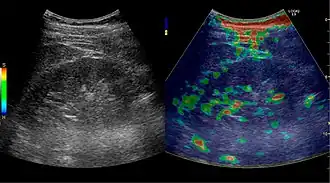

Contrast-enhanced ultrasound (CEUS) can evaluate microvasculature, which color Doppler US is unable to detect. In renal US examination, CEUS can be used to differentiate tumor and pseudotumor, such as prominent columns of Bertin. Pseudotumors enhance as adjacent renal tissue. The use of CEUS is recommended in special cases to distinguish between cystic and hypovascularized solid lesions, to characterize complex cysts, abscesses, traumatic lesions and ischemic lesions.[1]

Solid malignant tumors in the kidney do not exhibit specific enhancement patterns like some liver lesions, and no valid enhancement criteria between benign and malignant renal lesions have been proposed. However, CEUS is used in some patients after ablation of renal cell carcinoma to evaluate contrast uptake in the treated area (Figure 30).

Figure 31. Unspecific cortical lesion on CT is confirmed cystic and benign with contrast-enhanced ultrasound (CEUS) using image fusion.[1] -